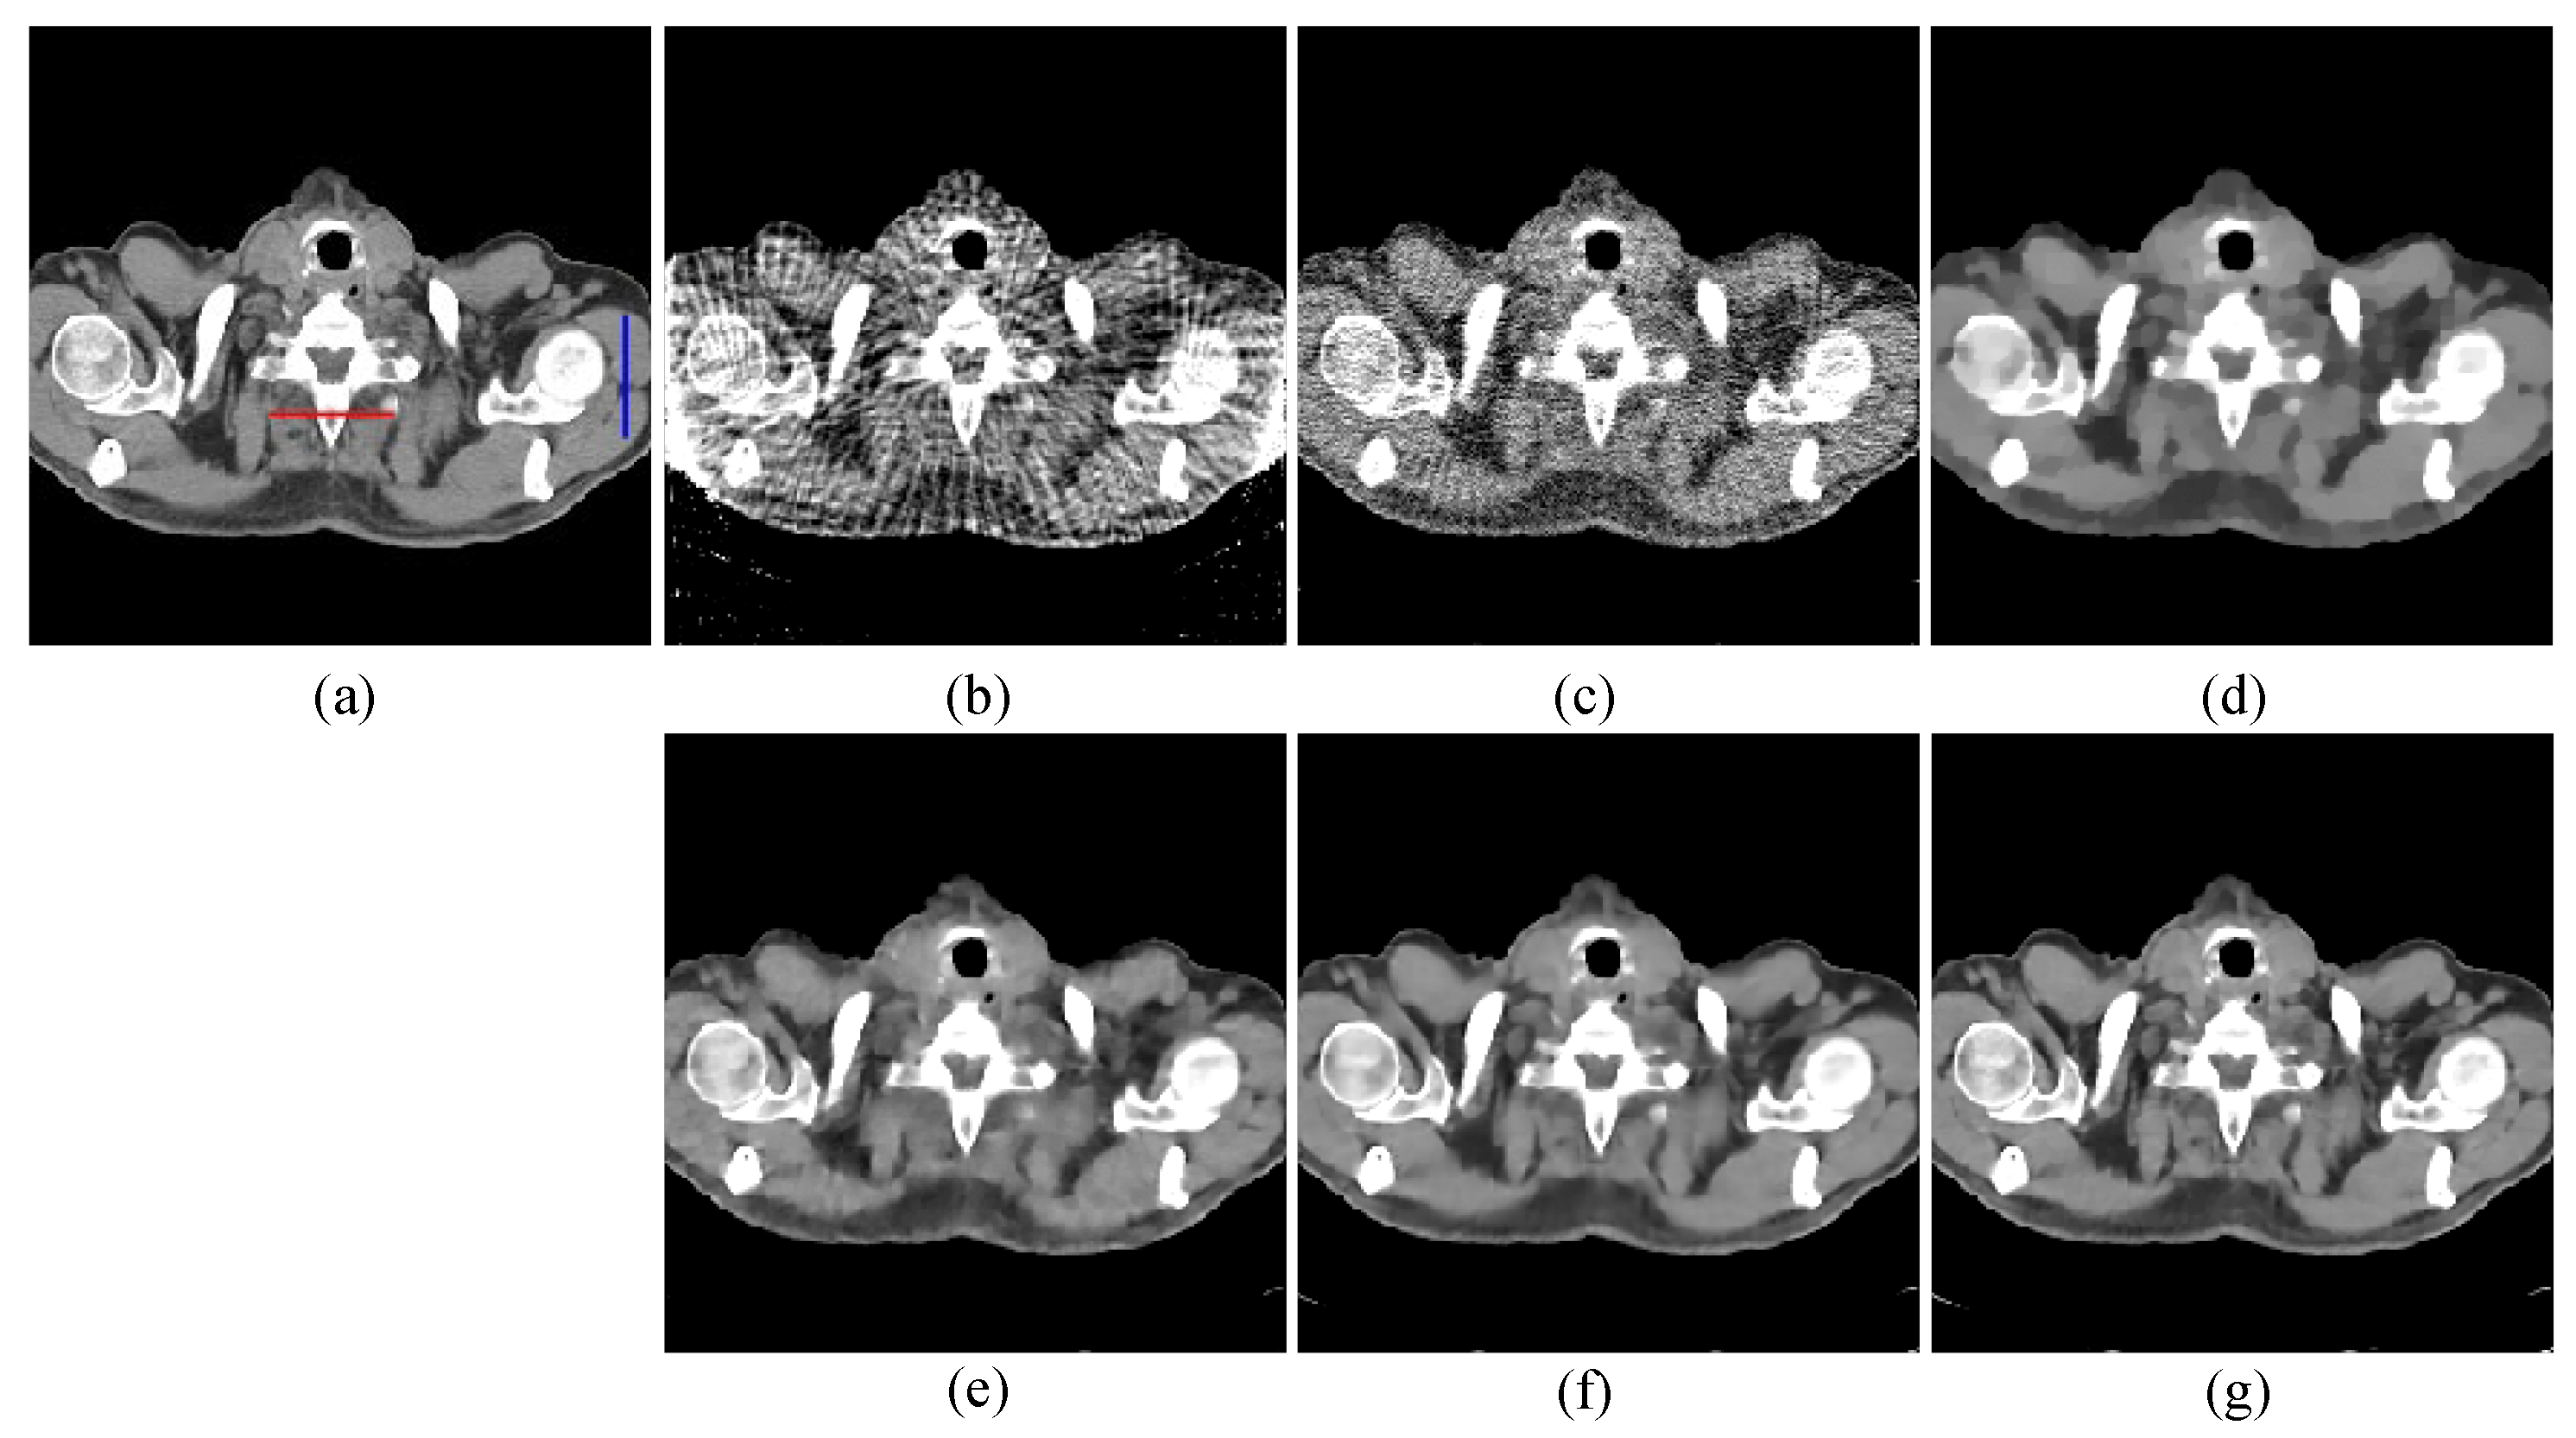

The first image reconstruction experiment is using a pelvic image to show the feasibility of our algorithm for SVCT reconstruction, as shown in Figure 1. We extracted 80, 64, and 48 views from a full scan and selected parameters empirically. The parameters are set as follows: a = 0.5, γ1 = 0.3, and γ2 = 0.08. Figure 2, Figure 3 and Figure 4 show the ground truth and reconstruction images via FBP, OS-SART, TV, PICCS, TVPI-G, and our method NPICCS. From these figures, it is evident that our algorithm outperforms the other methods in terms of recovering image structures and suppressing noise. Specifically, the FBP and OS-SART results (as shown in Figure 2b,c, Figure 3b,c and Figure 4b,c) contain high levels of noise and artifacts, while TV results (as shown in Figure 2d, Figure 3d and Figure 4d) are characterized by blurring and staircasing effects. The PICCS and TVPI-G methods provide better results than the other approaches because of the introduction of prior information, but image edges are missing as shown in Figure 2e,f, Figure 3e,f and Figure 4e,f. At the same time, it can be seen that our method is able to preserve image edges and suppress noise effectively, as shown in Figure 2g, Figure 3g and Figure 4g.

To visualize the accuracy of our proposed method for local reconstruction of CT images, we plot the one-dimensional line intensity distribution of CT images reconstructed from 80 projections at two areas (shown by the blue and red lines in Figure 4a), as displayed in Figure 6. It can be visually observed that the line intensity distribution of the reconstructed images from our proposed method is closest to the original CT images at the two areas. In comparison, the proposed reconstruction algorithm has higher accuracy.

Figure 4. 80 views reconstruction results of pelvic image: (a) ground truth, (b) FBP, (c) OS-SART, (d) TV, (e) PICCS, (f) TVPI-G, and (g) NPICCS. The display window is [−150 250] HU.